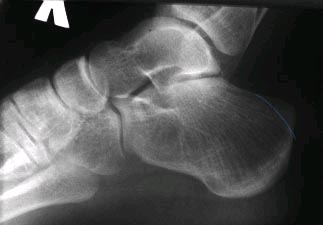

Я думаю объем резекции должен быть в таком объеме.

|

Спасибо всем, кто принимает участие в обсуждении случая. Досылаю рентгенограммы и МРТ. Хотелось-бы уточнить объем резекции пяточных костей.

Юрий Алексеевич Булахтин

Камчатский Военно-морской госпиталь